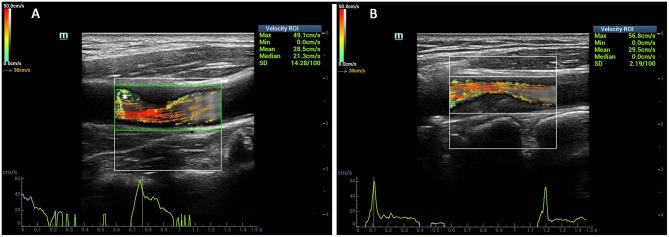

To investigate the value of high-frame rate vector flow imaging technique (V flow) in evaluating the hemodynamic changes of carotid stenosis caused by atherosclerotic plaques. In this prospective study, patients with stenosis rate (diameter) ≥30% caused by carotid atherosclerotic plaques were included. Degrees of carotid stenosis were graded according to North American Symptomatic Carotid Endarterectomy Trial criteria: moderate (30-69%) or severe (70-99%). Mindray Resona 7s ultrasound machine with a linear array transducer (3-11 MHz) was used for ultrasound examinations. The mean WSS value of carotid arteries was measured at the proximal, narrowest region and distal of carotid stenosis. The mean WSS values were correlated with peak systolic velocity (PSV) measured by color Doppler flow imaging and stenosis degree detected by digital subtraction angiography (DSA). The vector arrows and flow streamline detected by V flow dynamic imaging were analyzed. Imaging findings of DSA in carotid arteries were used as the gold standard. Finally, 51 patients were included. V flow measurements were performed successfully in 17 patients (100%) with moderate-grade stenosis and in 30 patients (88.2%) with severe-grade stenosis. Dynamic V flow imaging showed yellow or red vectors at the stenotic segment, indicating fast speed blood flow (up to 260.92 cm/s). Changes of streamlines were detected in the stenotic segment. The mean WSS value measured at the narrowest region of the carotid artery had a moderately positive correlation with stenosis degree ( = 0.58, < 0.05) and PSV value ( = 0.54, < 0.05), respectively. Significant difference was detected in mean WSS value at the narrowest region of the carotid artery between severe carotid stenosis (1.47 ± 0.97 Pa) and moderate carotid stenosis (0.96 ± 0.44 Pa) ( < 0.05). The hemodynamic changes detected by V flow of the carotid stenosis might be a potential non-invasive imaging tool for assessing the degree of carotid stenosis.

探讨高帧率矢量血流成像技术(V flow)在评估动脉粥样硬化斑块所致颈动脉狭窄血流动力学变化中的价值。在这项前瞻性研究中,纳入了颈动脉粥样硬化斑块导致狭窄率(直径)≥30%的患者。根据北美症状性颈动脉内膜切除术试验标准对颈动脉狭窄程度进行分级:中度(30%-69%)或重度(70%-99%)。使用配备线性阵列探头(3-11MHz)的迈瑞Resona 7s超声仪进行超声检查。在颈动脉狭窄的近端、最窄处和远端测量颈动脉的平均壁面切应力(WSS)值。将平均WSS值与彩色多普勒血流成像测量的收缩期峰值流速(PSV)以及数字减影血管造影(DSA)检测的狭窄程度进行相关性分析。对V flow动态成像检测到的矢量箭头和血流流线进行分析。以颈动脉DSA成像结果作为金标准。最终,纳入51例患者。17例中度狭窄患者(100%)和30例重度狭窄患者(88.2%)成功进行了V flow测量。V flow动态成像显示狭窄段出现黄色或红色矢量,表明血流速度较快(可达260.92cm/s)。在狭窄段检测到流线变化。在颈动脉最窄处测量的平均WSS值分别与狭窄程度(r = 0.58,P < 0.05)和PSV值(r = 0.54,P < 0.05)呈中度正相关。重度颈动脉狭窄(1.47±0.97Pa)与中度颈动脉狭窄(0.96±0.44Pa)在颈动脉最窄处的平均WSS值存在显著差异(P < 0.05)。V flow检测到的颈动脉狭窄血流动力学变化可能是评估颈动脉狭窄程度的一种潜在无创成像工具。